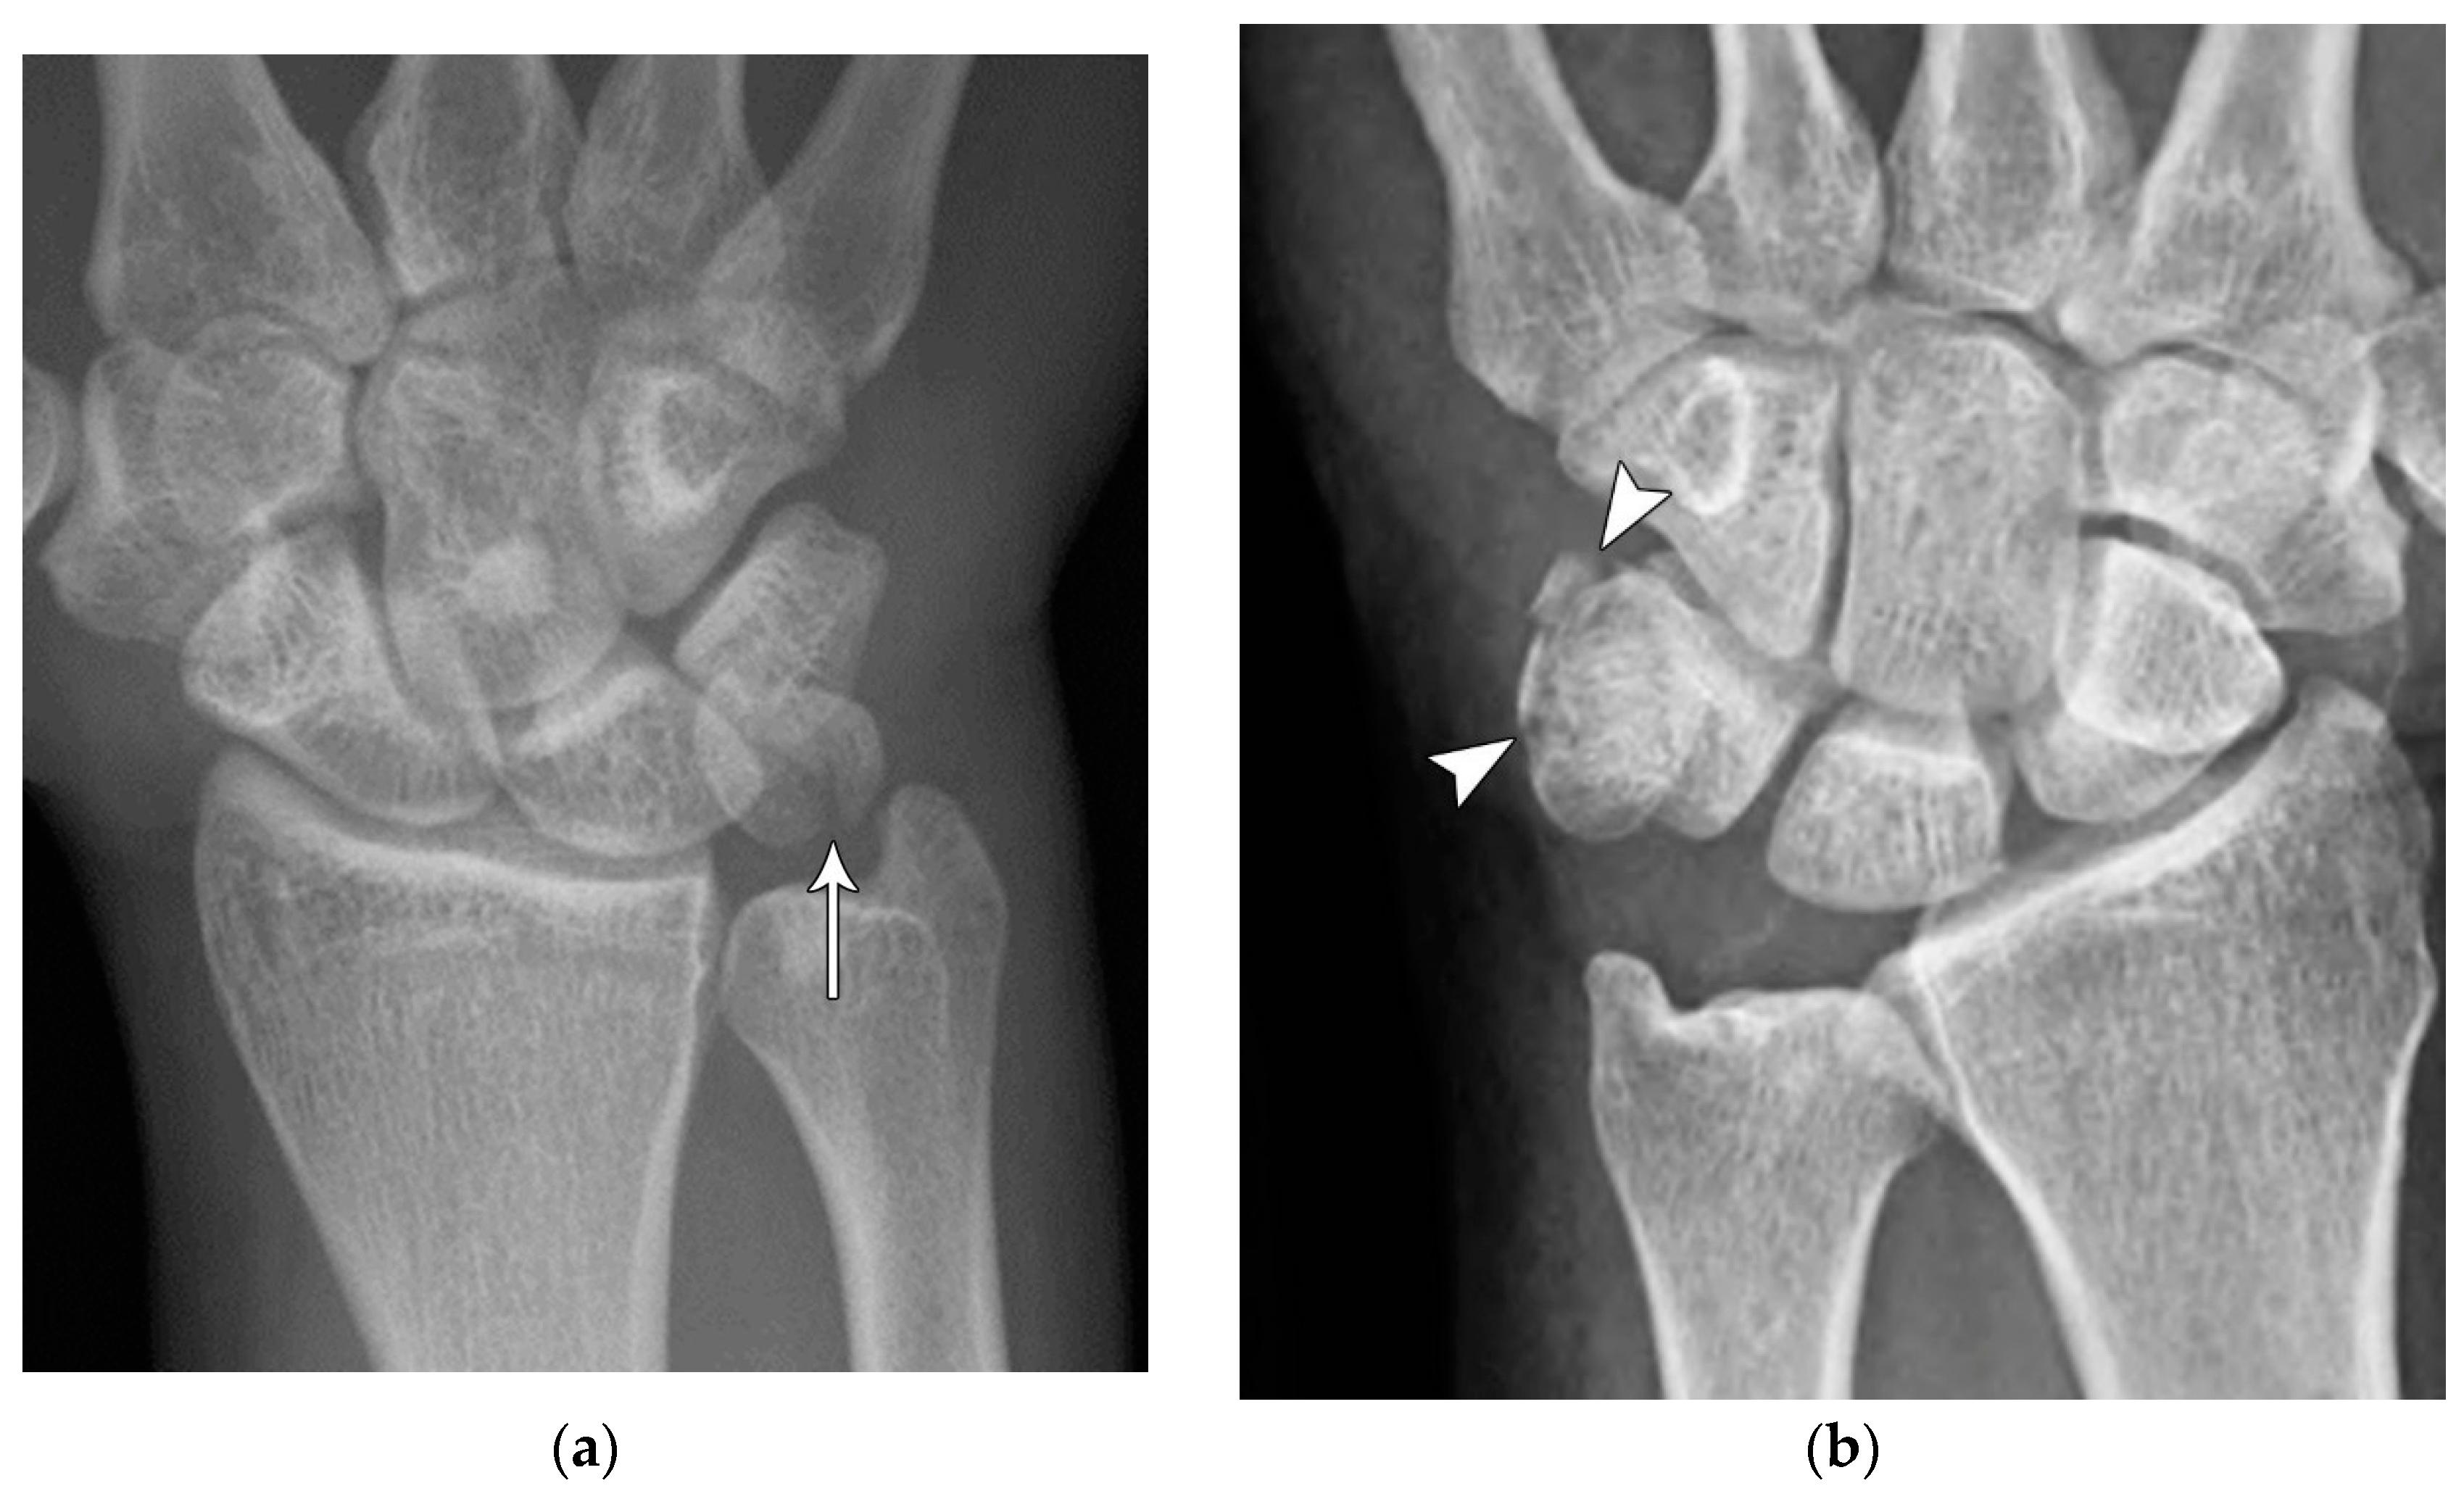

Common scaphoid fracture complications include avascular necrosis and nonunion [10]. Avascular necrosis is a dreaded outcome resulting from loss of the proximal arterial supply due to the distal entry point of nutrient vessels. This retrograde perfusion of the proximal pole makes it vulnerable to losing its vascular supply when fractured. Sclerosis of the proximal pole indicates osteonecrosis (Figure 5). With scaphoid nonunion, biomechanical alterations contribute to rapidly progressive degenerative arthritis and instability referred to as scaphoid nonunion advanced collapse (SNAC) [16]. Nonunion occurs in 5-10% of cases and has a higher incidence with displaced fractures (Figure 6). During wrist extension, the distal scaphoid fragment rotates into flexion while the proximal scaphoid fragment extends with the lunate. The resultant abnormal contact between the distal fragment and radius begins the first stage in degenerative collapse. This progresses into the second stage as scaphocapitate osteoarthritis develops and finally to the third stage with progression to capitolunate osteoarthritis and proximal radial migration of the capitate dorsal to the lunate. Treatment of SNAC wrists, depending on the degree and severity of the osteoarthritic collapse include scaphoidectomy with four-corner arthrodesis or wrist fusion [17]. Four-corner fusion helps reduce joint pain while maintaining some range of motion, as opposed to total wrist fusion (Figure 7).

Figure 5. (a) PA radiograph showing marked sclerosis (arrow) of the proximal pole of the scaphoid after a scaphoid fracture. (b) Coronal reformatted CT in a different patient showing sclerosis (arrow) of the proximal pole of the scaphoid after a scaphoid fracture, indicating osteonecrosis.